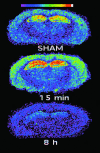

Traumatic brain injury is a leading cause of mortality and morbidity among young people. For the last couple of decades, it was believed that excess stimulation of brain receptors for the excitatory neurotransmitter glutamate was a major cause of delayed neuronal death after head injury, and several major clinical trials in severely head injured patients used blockers of the glutamate N-methyl-D-aspartate (NMDA) receptor. All of these trials failed to show efficacy. Using a mouse model of traumatic brain injury and quantitative autoradiography of the activity-dependent NMDA receptor antagonist MK801, we show that hyperactivation of glutamate NMDA receptors after injury is short-lived (<1 h) and is followed by a profound and long-lasting (> or =7 days) loss of function. Furthermore, stimulation of NMDA receptors by NMDA 24 and 48 h postinjury produced a significant attenuation of neurological deficits (blocked by coadministration of MK801) and restored cognitive performance 14 days postinjury. These results provide the underlying mechanism for the well known but heretofore unexplained short therapeutic window of glutamate antagonists after brain injury and support a pharmacological intervention with a relatively long (> or =24 h) time window easily attainable for treatment of human accidental head injury.